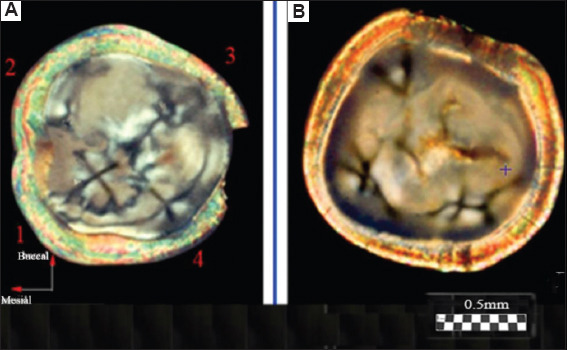

Results: The dentinal tubules were shown to originate from the center of the cusps in both molar and premolar teeth, forming S-shaped fiber bundles with axial-radial symmetry. These bundles were arranged along axes, extending from the pulp toward the centers of the cusps of the tooth crown. Within these zones, distinct optical patterns resembling conoscopic figures in the form of a "Maltese cross" were observed. This indicates a highly ordered architecture composed of optically anisotropic uniaxial tubules. The optical data were correlated well with findings obtained by electrometric and ion diffusion methods, including dentinal tubule staining.